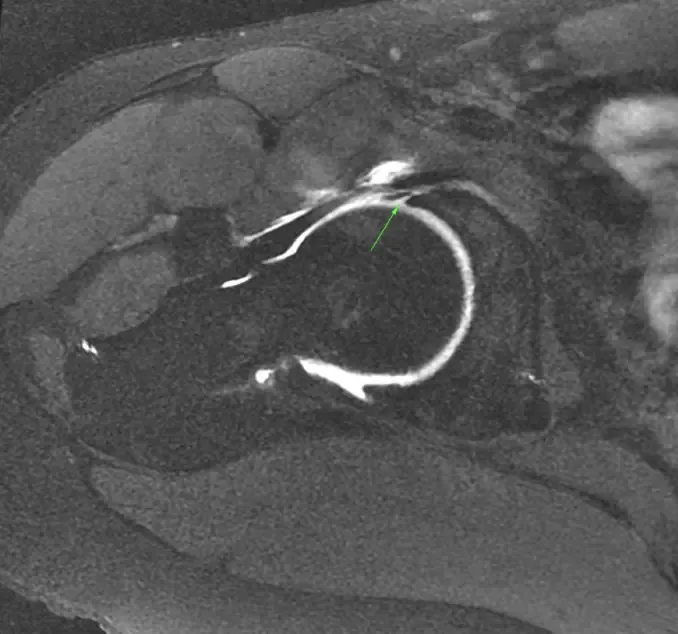

Femoroacetabular impingement syndrome (FAIS) is a condition characterized by abnormal and dynamic contact between the femoral head–neck junction and the acetabular rim, caused by altered bone morphology such as cam, pincer, or mixed types. This abnormal contact results in progressive damage to the acetabular labrum, chondrolabral junction, and articular cartilage, potentially leading to hip joint degeneration and osteoarthritis. Diagnosis of FAIS is based on a triad of patient symptoms (such as pain, clicking, stiffness, and limited range of motion), specific clinical maneuvers (including the flexion adduction internal rotation and flexion abduction external rotation tests), and imaging studies (orthogonal hip and pelvis X-rays, and MRI or arthrograms). Initial treatment is often conservative, involving physical therapy, intra-articular injections, and activity modification. When conservative management fails or specific criteria are met, surgical treatment, primarily hip arthroscopy, which is a minimally invasive surgical procedure, is performed to correct bony abnormalities and repair or reconstruct labral lesions, aiming to preserve hip function and alleviate symptoms.